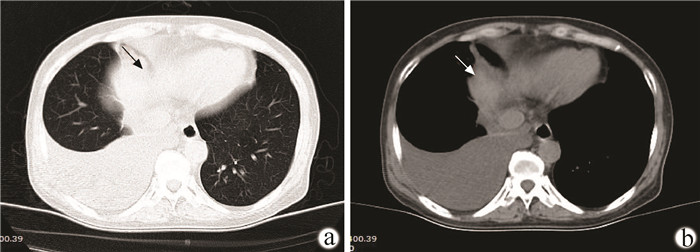

肝硬化失代偿期合并恶性胸膜间皮瘤并腹膜转移1例报告

卢利霞, 谢小青, 郑英, 刘鑫, 王建平, 王俊科, 王盼, 于晓辉

2022, 38(2): 418-419. DOI: 10.3969/j.issn.1001-5256.2022.02.030

摘要(913) HTML (261) PDF (2461KB)(58)

摘要: